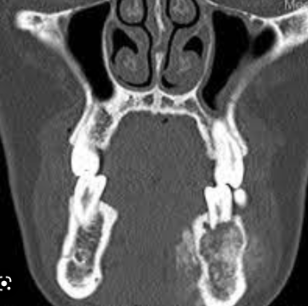

Give a differential diagnosis for the following radiographic image:

(multilocular radiolucency in right posterior mandible)

A

1. Odontogenic keratocyst

2. ameloblastoma

3. central giant cell granuloma